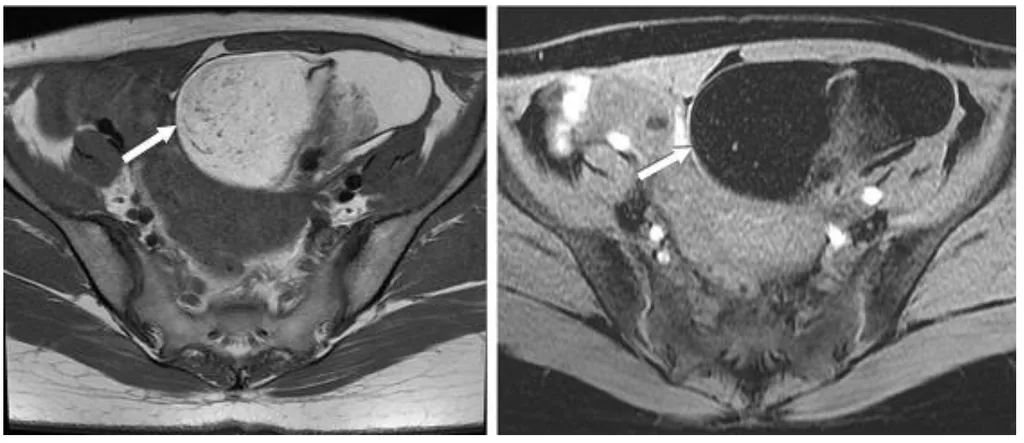

【114-2 醫學(六) 第74題】一位年輕女性接受磁振造影檢查發現卵巢腫瘤如圖,箭號所指之病灶,下列何者為最恰當之診斷?

詳解

破題關鍵

這道題的解題核心在於辨識磁振造影(MRI)影像中卵巢腫瘤特有的「脂肪訊號」,這是畸胎瘤最典型的影像學特徵。圖片中左側影像顯示病灶內部有高訊號(亮白色)區域,而右側影像在脂肪抑制序列下,這些區域訊號變暗,明確指出病灶含有脂肪成分。

選項拆解